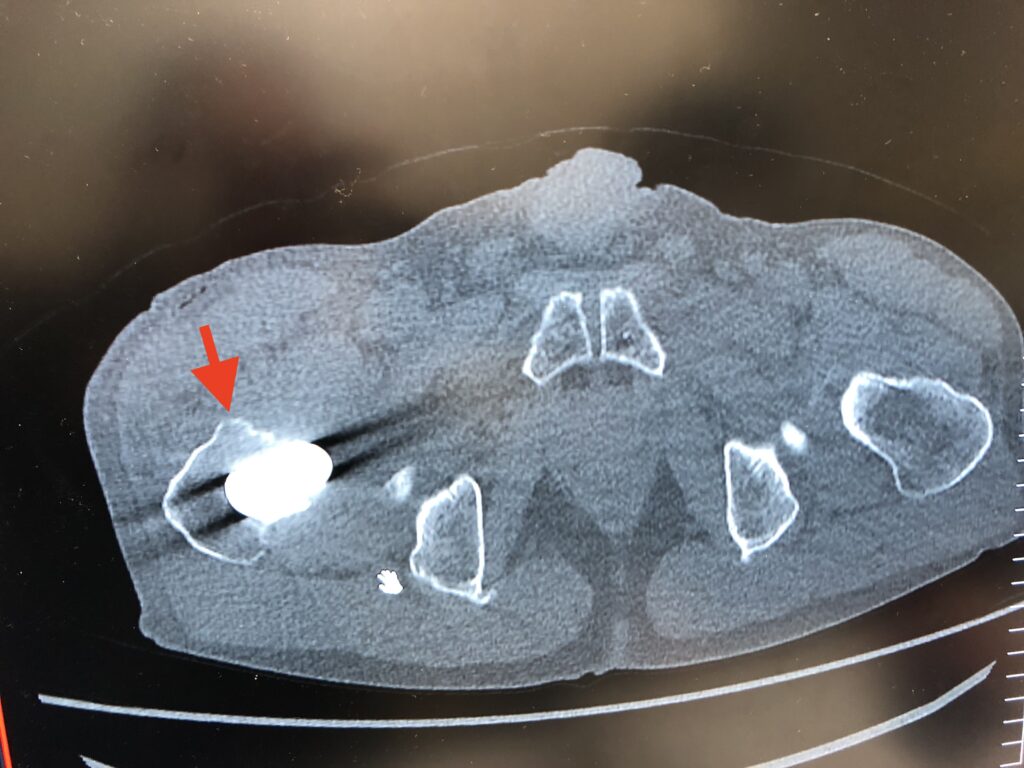

右股関節を屈曲(膝を曲げて胸に近づける)していくと外旋(膝が外側に向いてしまう)してしまうのはなぜか。

Dr.:それは右脚の大腿骨の先端が変形していて骨盤にぶつかってしまうから。

tao:それは術前に都内のクリニックで保存治療で散々やったリハビリで現在もキャット&ドッグとバード&ドッグはやっています。手術のときにその変形した骨をカットすることはできなかったのですか。

Dr.:カットできる場所ではなかった。

股関節をまっすぐ屈曲していくと屈曲約90°で大腿骨頸部と関節唇がインピンジメントする?

まず初めに正しい股関節の屈曲方法について説明しておきます。股関節屈曲は、まっすぐ曲げるのではなく大腿骨頸部を軸とし、外転・外旋方向に曲げていくのが正しい方法です。

これは何故かというと、股関節をまっすぐ屈曲していくと屈曲約90°で大腿骨頸部と関節唇がインピンジメントするからです。